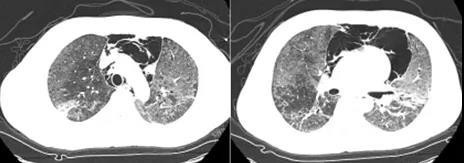

入院后给予无创呼吸机辅助呼吸,模式CPAP,给氧浓度85%,压力支持12 cmH2O。患者为年轻男性,长期应用糖皮质激素及免疫抑制剂,发热、呼吸困难,氧合指数约为136 mmHg,考虑患者出现重症肺炎可能性大,急查胸部CT可见两肺透亮度减低,两肺片状密度增高影,两下肺伴有实变,双侧胸腔及纵隔内积气(图1)。

图1 患者胸部CT(2017-07-03)